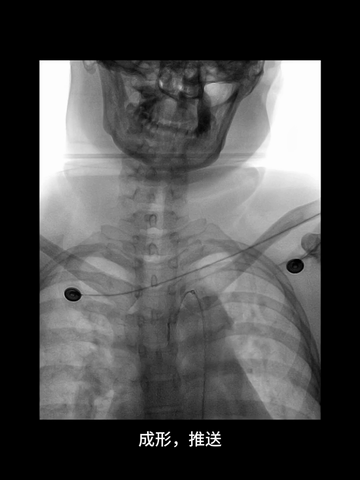

右股动脉穿刺置入8F短鞘,125cm长度5F多功能管塑成西蒙管头端形状,与6F长鞘(Cook,90cm)组成同轴,导丝导引下,5F管进入左锁骨下动脉,而后成其头端成西蒙管形,进入弓内。

西蒙管形头端超选入无名动脉,回拉导管时,习惯性进入右锁骨下动脉,间断冒烟下退回无名动脉,在旋转导管调整头端方向时,管头弹回弓内。

西蒙形管后续超选过程中,导管头还是习惯性进入左锁骨下动脉,调整导管头方向过程中,头端易弹回弓内。

耐心冒烟下,调整导管头在无名动脉内指向左侧,同时回拉导管,进入右CCA,后上高导丝,长鞘沿5F管顺利进入右CCA,后在导管导丝导引下,长鞘头端上高到右C1远端,建立可靠的治疗通路。